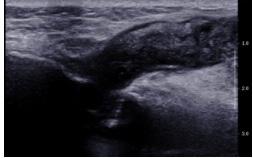

Mammogram Left MLO view shows a circumscribed high-density round to oval lesion in the upper quadrant near the axillary tail. Another partially visible high-density lesion is seen in the lower inner quadrant posterior third of the breast ( retroglandular zone) near the chest wall. Corroborative USG of the upper outer quadrant lesion revealed a hypoechoic round to oval lesion with microlobulated margins while the lower inner quadrant lesion revealed an anechoic collection with fine internal echoes reaching up to the chest wall with areas of bone erosion of the sternum. CT was done to see the extent of collection and other lesions which showed a hypodense collection in the chest wall near the sternum with areas of bone erosion and a hypodense round to oval lesion near the axillary tail. PET CT was done for academic purposes which showed uptake from the chest wall lesion near the sternum with no uptake in the hypodense collection. Biopsy was done from both the upper outer quadrant and chest wall lesion.